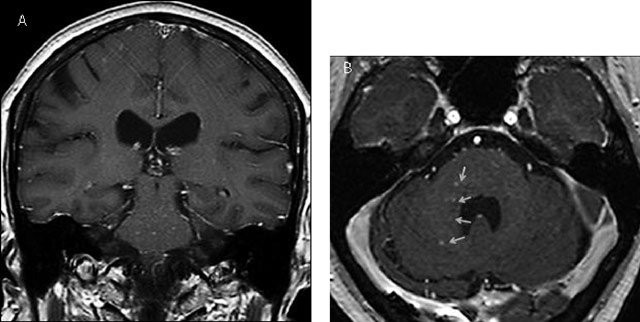

Figure 3

Coronal (A) and axial (B) contrast-enhanced T1 MRI images after 1.5 years showing new punctate and curvilinear lesions predomanintly in the pons and the right middle cerebellar peduncle (yellow arrows).